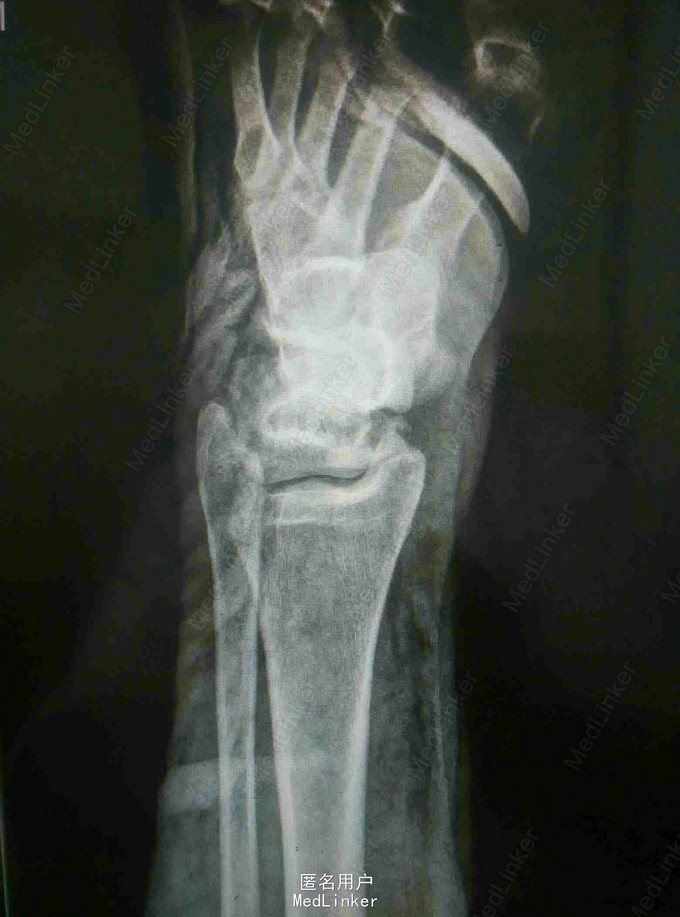

患者外伤致左踝关节疼痛肿胀,活动受限2天 患者中年女性,因外伤致左踝关节疼痛肿胀,伤后即无法站立,踝关节活动受限,于当地医院石膏外固定后入我院。

查体:左踝关节肿胀明显,局部皮肤压痛,无皮损及皮下淤斑,踝关节活动受限,各足趾感觉正常,足背动脉搏动存在。 辅查:我院CT提示距骨、足舟骨、跟骨骨折

诊断:左足距骨、足舟骨、跟骨骨折 治疗:距骨骨折切开复位内固定术

随访:石膏固定4-6周,3月内禁止负重,定期复查。 讨论:患者X线片对左足骨折显示不够清楚,基本常规行CT,可以看到明显的距骨骨折,累及关节面,需手术复位关节面。足舟骨以及跟骨骨折未明显移位保守处理。